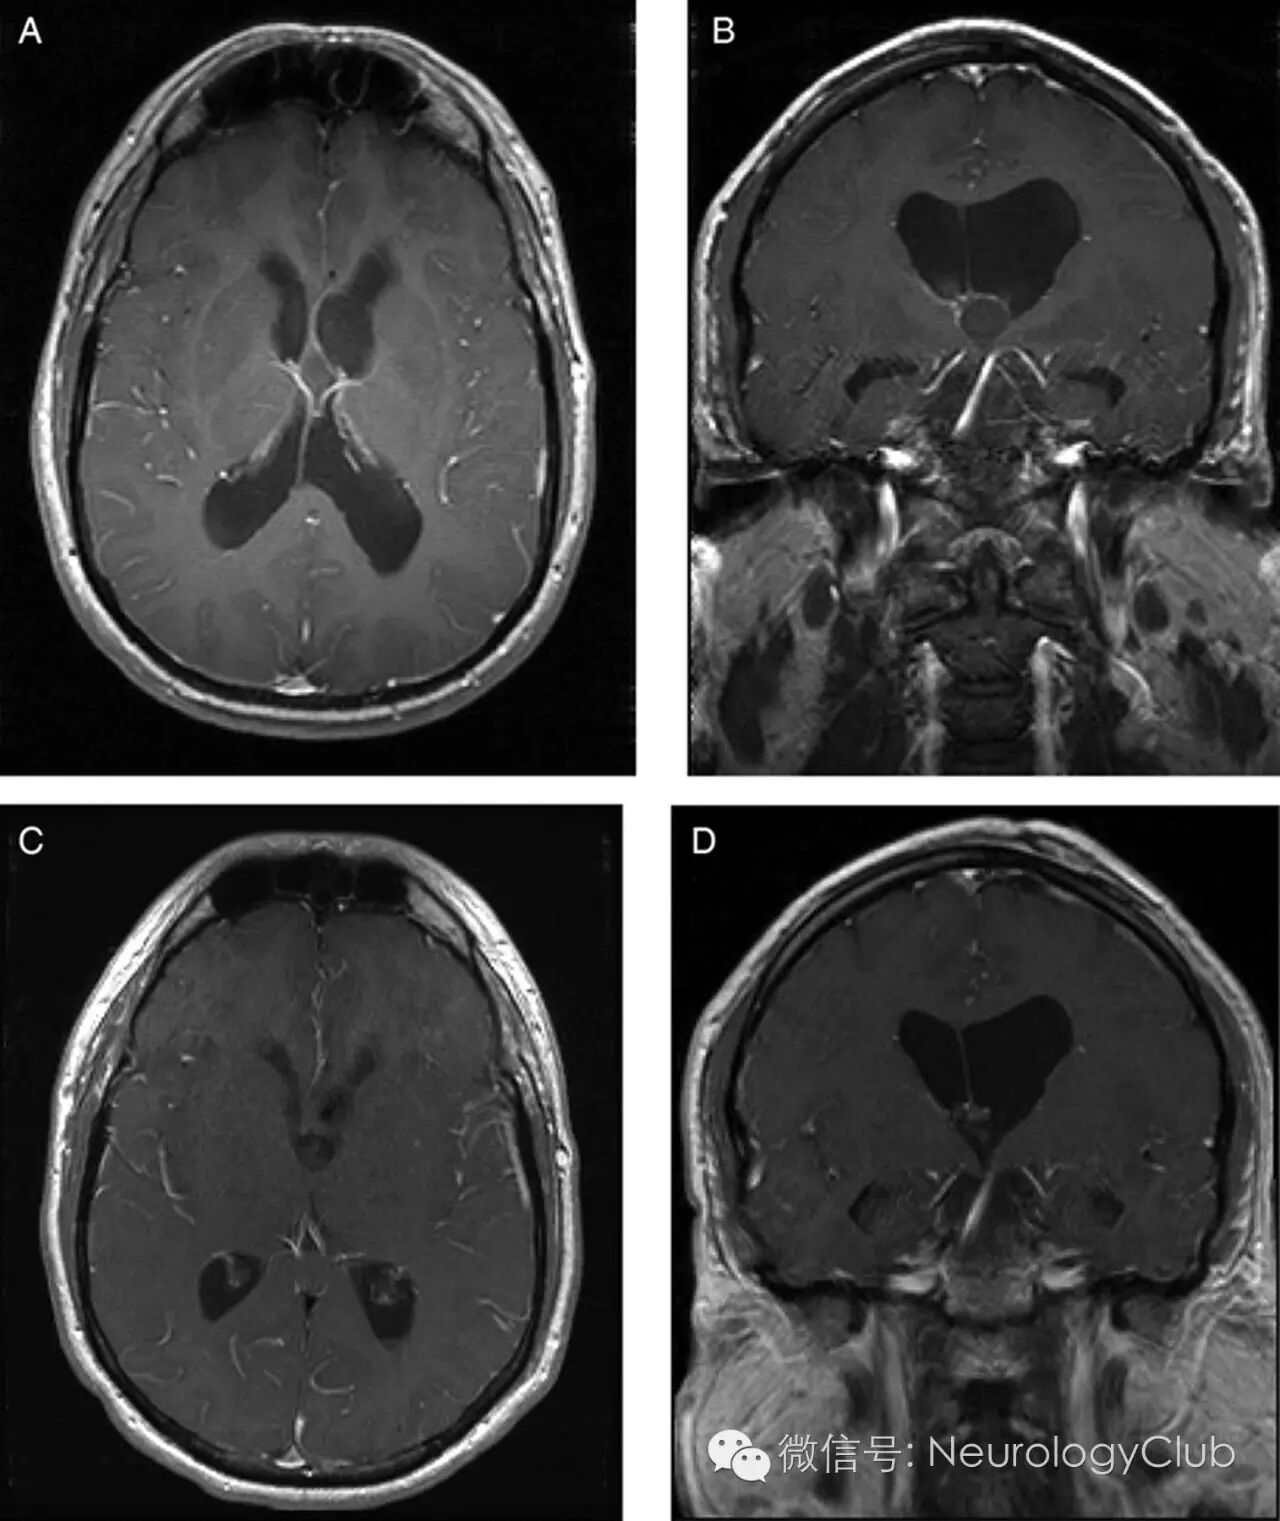

26岁女性,表现为间歇性并逐渐加重的头痛2年。头颅MRI提示三脑室1.1cm囊性,周围强化病灶,位于脑室间Monro孔(图1A,B),导致梗阻性脑积水。患者行内镜下经额钻孔脑室内病灶切除术,病理证实为胶样囊肿。内镜术后,患者恢复良好(图1C,D,术后MRI),头痛症状改善。

(图:A-B:术前MRI,T1增强,横断面和冠状位可见脑室扩大,Monro孔圆形,周围强化囊性病灶;C-D:术后MRI,T1增强,横断面和冠状位可见胶样囊肿已经切除